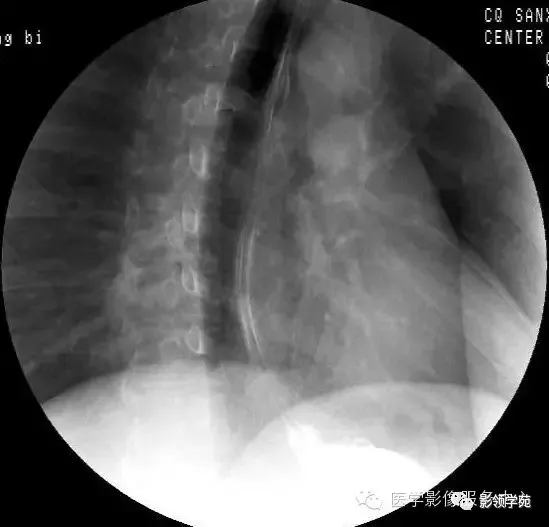

1.食管钡餐造影 根据钡餐造影的影像特点,食管狭窄可分两型.

10种食管钡餐常见疾病图解